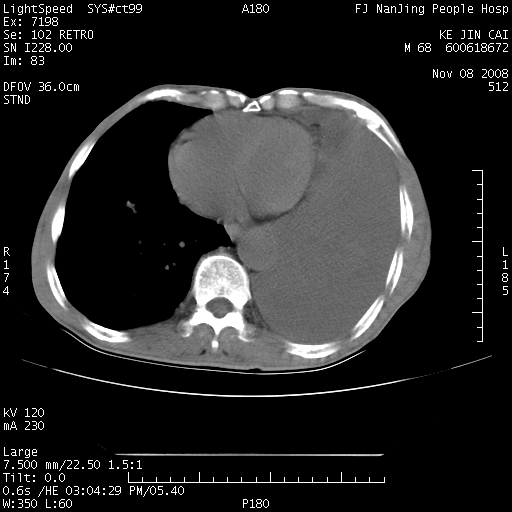

是个很有看头的病例,咋人气那么不旺?没多少人兴趣呢?这个病例几大怪:1   恶性肿瘤侵犯心肌左房怪,心肌一般不会被恶性肿瘤侵犯吧?2   左下肺均匀实变怪,内无含气,有别一般不张实变,含气肺泡完全为液体取代,而非一般不张实变的肺萎陷,冷不丁还以为是肿大的脾脏3   肿瘤本身怪,像tb肺不张4   这么有看头的病例没人气怪。呵呵。

左肺恶性肿瘤侵犯肺动脉,左心房内瘤栓,胸膜转移。

左肺恶性肿瘤侵犯肺动脉,左心房内瘤栓,胸膜转移,少见,学习了。